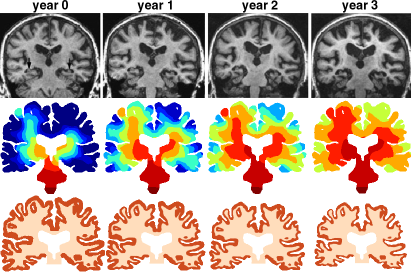

Shrinking: We now turn to the effect of elevated toxic proteins on the tissue. It is known that the formation of large aggregates or high concentration of toxic proteins prevents the proper function of neuronal cells, leading to ischemia, and eventually tissue removal. For instance, in the top row of Fig. 5, there is a marked and rapid atrophy associated with the disease. We use our propagation model on a similar coronal slice to compute the activation time at three different time points (middle row). For each of these time points we compute the shrinking of the slice and show the change in geometry from the previous one (bottom row). The degeneration-induced atrophy patterns (bottom row) agree well with the atrophy pattern observed in Alzheimer’s disease (top row).

Refer to caption

Figure 5: Atrophy. Top row: magnetic resonance images showing hippocampal atrophy in Alzheimer s disease Lehéricy et al. (2007): yearly examination of the same subject is shown. Increasing hippocampal and atrophy is observed together with ventricular enlargement and widening of cortical sulci. Middle row: activation time based on initial seeding in the brain stem. Bottom row: shrinking based on the activation time and toxic protein concentration with a ratio ϑgray:ϑwhite=4:1:subscriptitalic-ϑgraysubscriptitalic-ϑwhite4:1\vartheta_{\text{gray}}:\vartheta_{\text{white}}=4:1.